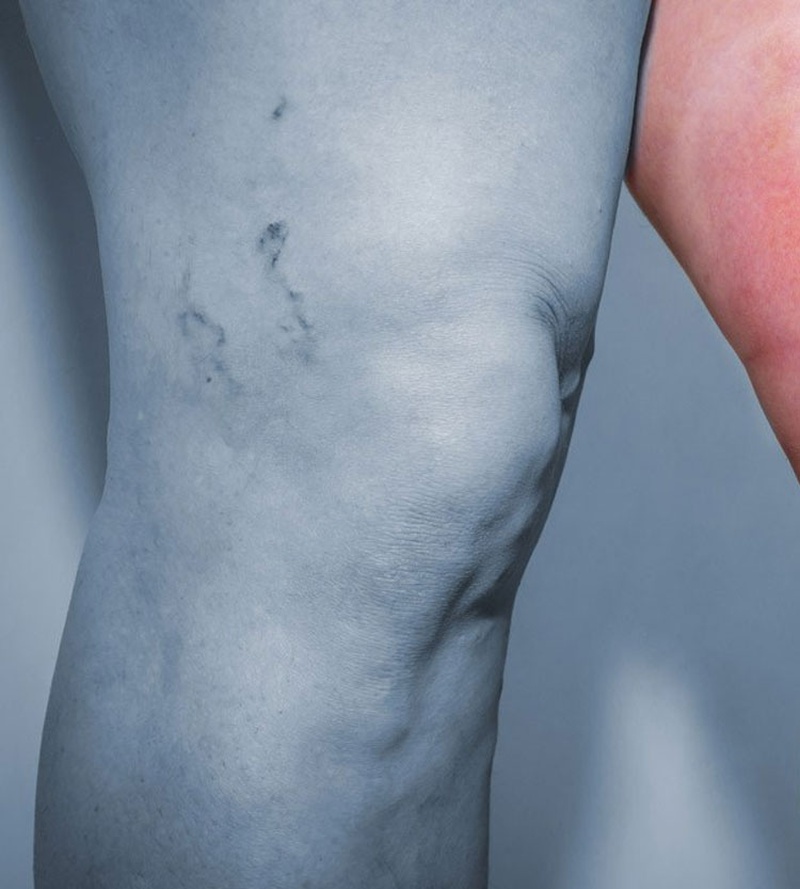

Варикозна хвороба - це патологічне розширення вен, що знаходяться на поверхні, яке характеризуються збільшенням їх діаметру і довжини, що в результаті призводить до циліндричного, змієподібного, мешковидного і змішаного типу зміни венозних стовбурів.

Захворювання має хронічний характер із прогресуючим перебігом і незворотними змінами в підшкірних, комунікантних та глибоких венах, і як наслідок, у шкірі та м’яких тканинах кінцівок. Переважно хвороба проявляється в молодому віці та з часом лише прогресує, повністю зупинити цей процес неможливо. Частота захворювання становить від 13 до 25 % дорослого населення. Жінки хворіють утричі частіше, ніж чоловіки. Це, в основному, пояснюється анатомічними особливостями організму і певними навантаженнями на нижні кінцівки в період вагітності. «Патологічне коло», що розвивається у варикозно уражених венах, призводить до постійного розширення стінок вен, збільшення їх просвіту, отже, поглиблює недостатність клапанного апарату і спричиняє ретроградне скидання венозної крові, її застій, порушення трофіки у тканинах кінцівок. Відмова від своєчасного лікування неминуче призводить до розвитку ускладнень. Здебільшого це гострий тромбофлебіт поверхневих вен, гострі тромбози глибоких вен нижніх кінцівок, постромбофлебітичний синдром (ПТФС), кровотечі з варикозно розширених вен тощо. Найзагрозливішим ускладненням варикозної хвороби є розвиток гострого тромбофлебіту у змінених підшкірних венах, що може призвести до фатальної тромбоемболії легеневої артерії та смерті пацієнта.